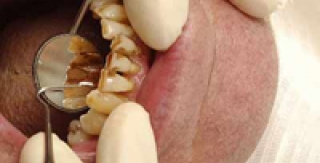

Nha chu là bệnh của các mô quanh răng. Nếu không được điều trị, bệnh tiến triển đưa đến mất răng. Bệnh nha chu tiến triển chậm, không có các dấu hiệu gì đặc biệt, không đau, hoặc ít đau nên nhiều người thường bỏ qua. Tuy nhiên, hậu quả do bệnh nha chu gây ra lại đặc biệt nghiêm trọng, nếu được chẩn đoán và điều trị sớm có thể giảm nhẹ nguy cơ mất răng. Nguyên nhân...

Nha chu liên quan trực tiếp đến mô nâng đỡ quanh chân răng, bao gồm bệnh của nướu và các bệnh lý phá hủy mô nâng đỡ sâu bên dưới nướu (xương ổ răng, dây chằng nha chu...). Nha chu là nguyên nhân quan trọng gây mất răng. Phòng ngừa bệnh nha chu Bệnh thường diễn biến qua 2 giai đoạn: viêm nướu và viêm nha chu. Nếu nướu bị viêm, ta sẽ thấy một hoặc nhiều dấu hiệu sau: - Nướu đổi màu so với...